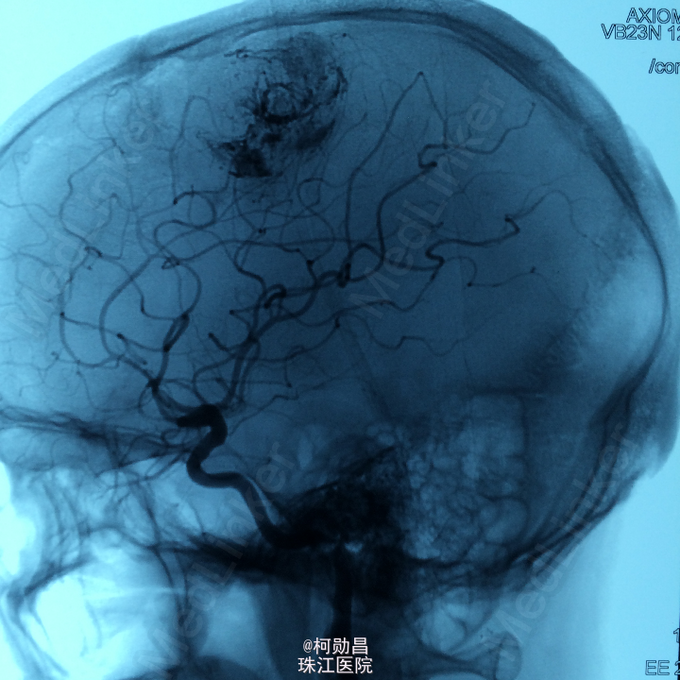

主诉:头痛伴右上肢麻木无力两个月,加重七天 病史:两个月前出现头痛,走路不稳,右上肢无力,不能持物,过去两个月曾有两次癫痫全面发作,发作时意识丧失,但无尿失禁及舌头咬伤。查头MRI示右侧顶叶占位,考虑脑膜瘤。

查体:巴氏征阳性,左侧肢体感觉减退,肌力正常,余无特殊阳性。 辅助检查:查头MRI示右侧顶叶占位,考虑脑膜瘤。

诊断:左侧顶叶占位 处理:行DSA检查,提示肿瘤染色,予PVA颗粒行血管内栓塞治疗。

术后再予开颅手术治疗,书中见供血动脉闭塞,出血量少。